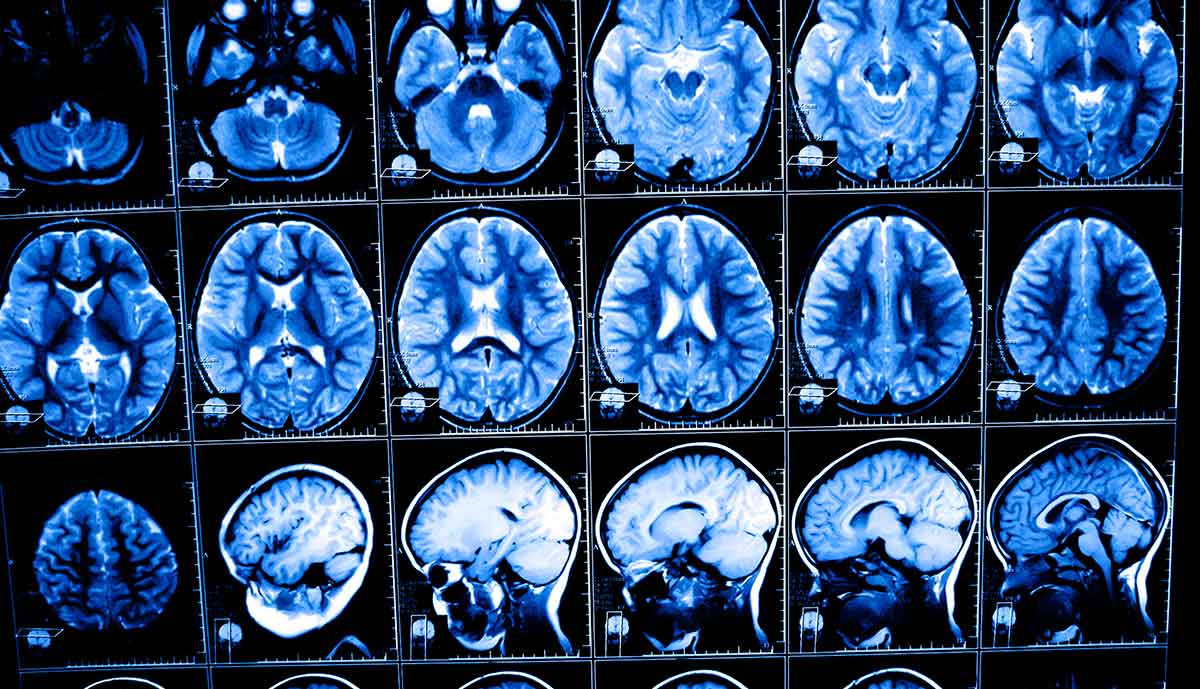

Разница между проявлениями невроза и настоящей шизофренией заключается еще и в изменении головного мозга: его исследование показало наличие органических изменений у шизофреников и их отсутствие у невротиков. По мере прогрессирования степени психического отклонения у больного наступает распад личности: он отдаляется от общества, становится вялым, безэмоциональным. При невротических расстройствах характер и свойства личности не меняются.